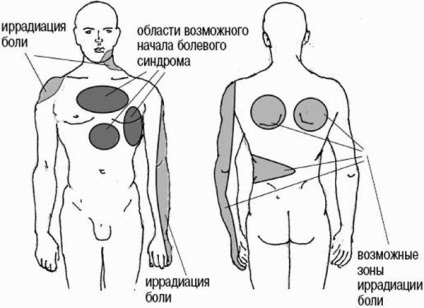

Lehetséges területek sugárzó fájdalommal